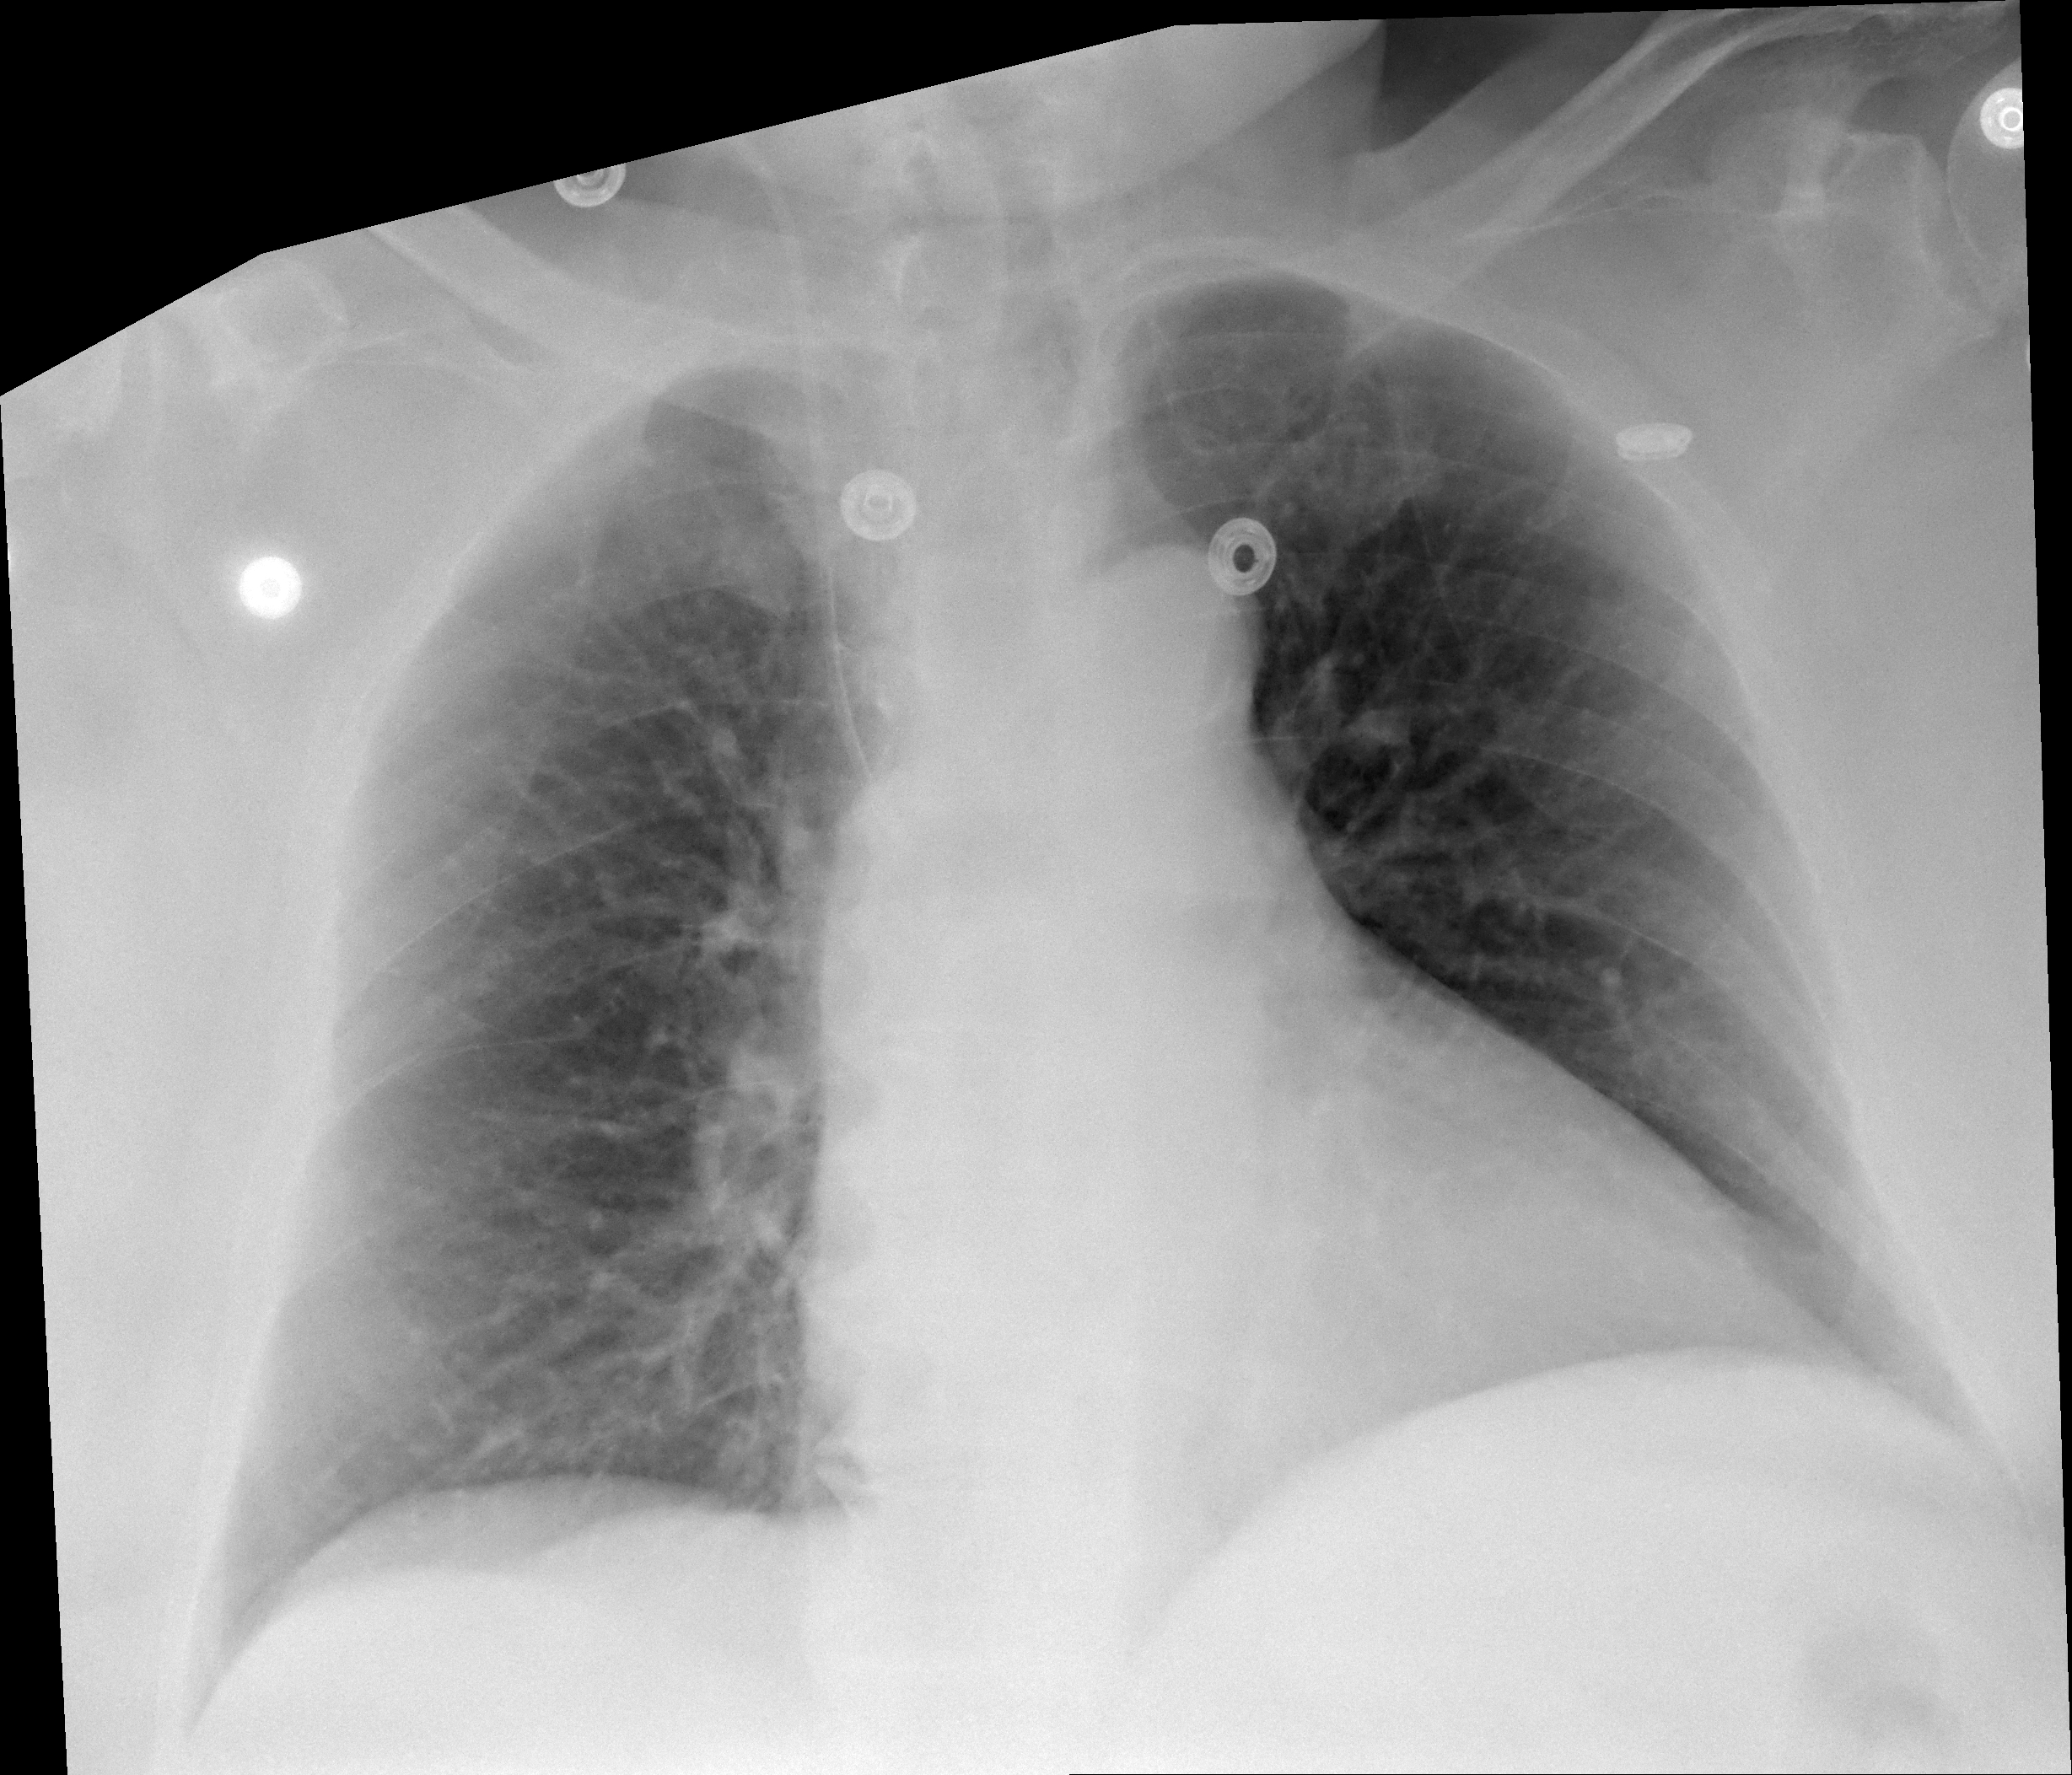

21.02.2026

Bett-Thorax (2 Tage postoperativ)

1 Aufnahme | 2457x2105 px

21. Februar 2026

Bett-Thorax

Röntgen-Thorax 2 Tage nach OP.

21.02.2026 - POSTOP

DICOM

Thorax-Röntgen 2 Tage nach Wiedereinbau TEP